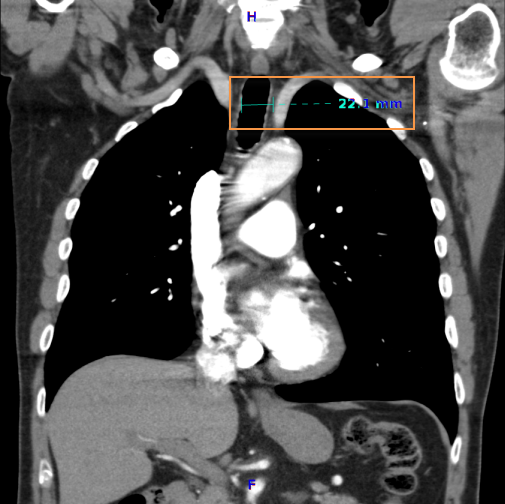

To obtain a distance measurement:

![]() - Measure Distance

- Measure Distance